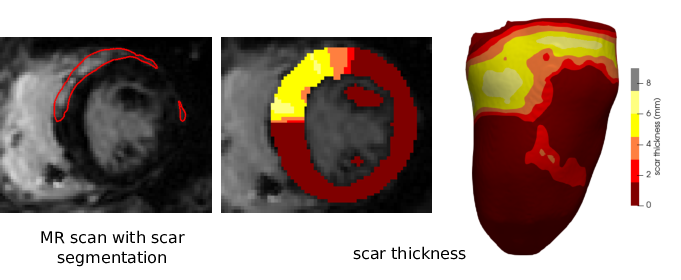

Figure 5: Scar thickness. From left to right: MR image with late gadolinium enhancement typical of scar tissue (outlined in red); scar thickness visualise overlayed on a MR slice; scar thickness projected on a surfacic mesh

Our method can also be used to quantify the local thickness of an infarct scar. To achieve this, after segmentation of the endocardial and epicardial masks, one has to segment the scar mask (how to obtain such segmentation is outside the scope of this article).

The weight function \(f\) is then defined such that \(f(x) = 0\) in the myocardium and \(f(x) = 1\) in the scar. This can be used to visually assess the thickness of the fibrosis, as shown on fig. 5